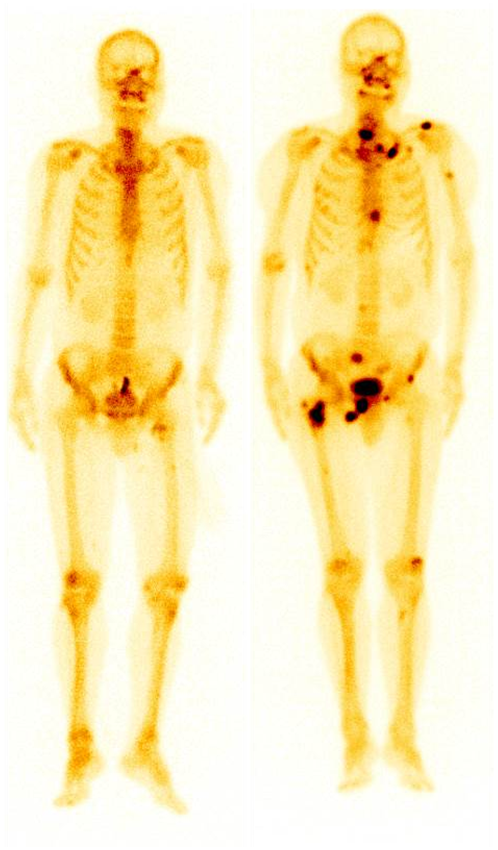

肺腺癌患者,左圖為2018年12月ECT,未見明顯異常;期間未復(fù)查;2023年5月骨痛來診,ECT顯示全身多發(fā)骨轉(zhuǎn)移(右圖)。

SPECT全身骨顯像在早期診斷腫瘤骨轉(zhuǎn)移方面具有明顯優(yōu)勢,能及早發(fā)現(xiàn)病變,有利于精準(zhǔn)有效的治療。隨著腫瘤治療方式的不斷進步,腫瘤患者生存期越來越長,相應(yīng)發(fā)生骨轉(zhuǎn)移的風(fēng)險也隨之增高,早期發(fā)現(xiàn)骨轉(zhuǎn)移并進行針對性治療,能夠極大改善患者生存質(zhì)量。